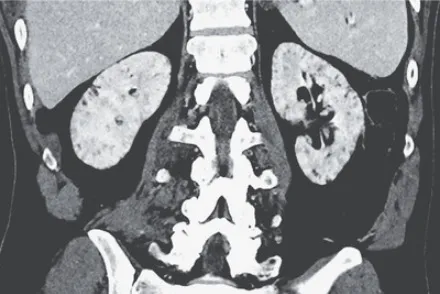

Uma causa incomum de hematúria glomerular intermitente!

Hematúria pós infecção, caso clínicos para auxiliar no entendimento de causas glomerulares comuns e raras...